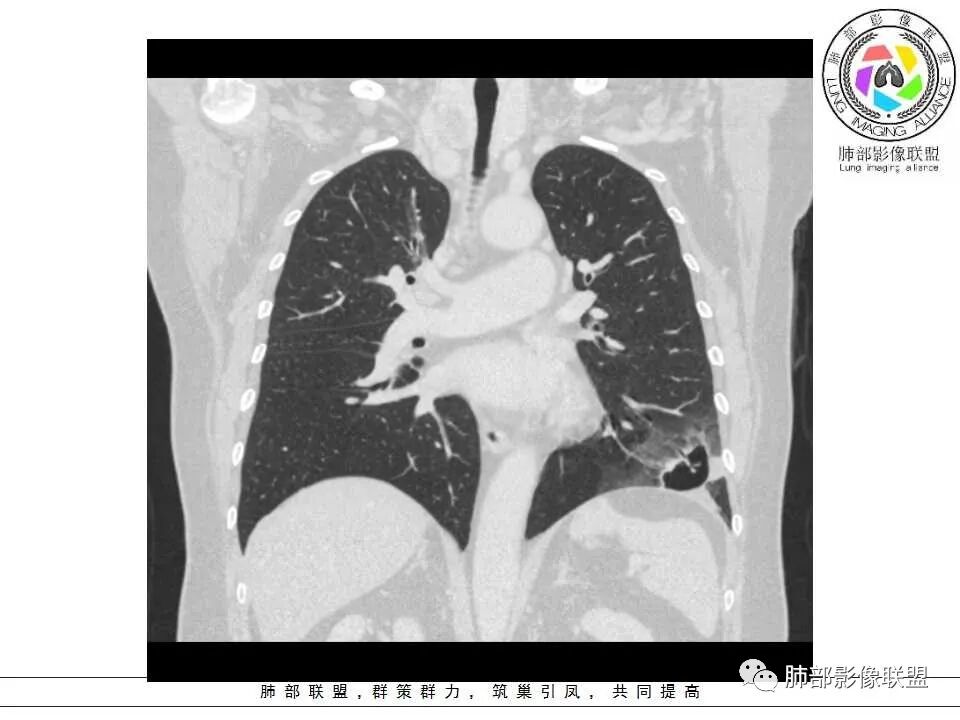

女性,65岁,咳嗽、咳痰2月余,伴发热数日。

胸CT:左肺下叶囊腔,壁厚薄不均,可见壁结节,囊腔内可见断裂小梁,部分融合,周围边界较清楚GGO,胸膜牵拉,可见血管集束、支气管充气征,冠状位部分层面可见支气管在囊腔边缘截断。考虑:囊腔型腺Ca。鉴别:肺大疱感染,CPAM等。

患者,女,65岁,2月余前受凉感冒后开始出现咳嗽,咳白痰,初发热2天,体温38℃左右,后降至正常,咳嗽无好转。近2日咳嗽加重,痰量增多,为黄白痰,无发热,无乏力、盗汗,无胸痛、胸闷,无头晕、头痛,无恶心、呕吐。PET-CT检查提示炎性病灶与恶性结节鉴别困难。

病灶分两部分

周围大片GGO

中央囊实性病变

1、左肺下叶外基底段不规则囊腔样病灶,囊腔内有条形影及血管穿行。

2、囊壁薄厚不均匀,稍显僵硬,有壁结节(对应边缘分叶等)、结节强化明显。

以上两条几乎将肺囊肿彻底排除在外,且高度怀疑新生物!

3、灶周环以大范围磨玻璃影,非常均匀,没有重力分布趋势,分叶状,边界隐约可变。

4、冠状位部分层面可见支气管在囊腔边缘截断。